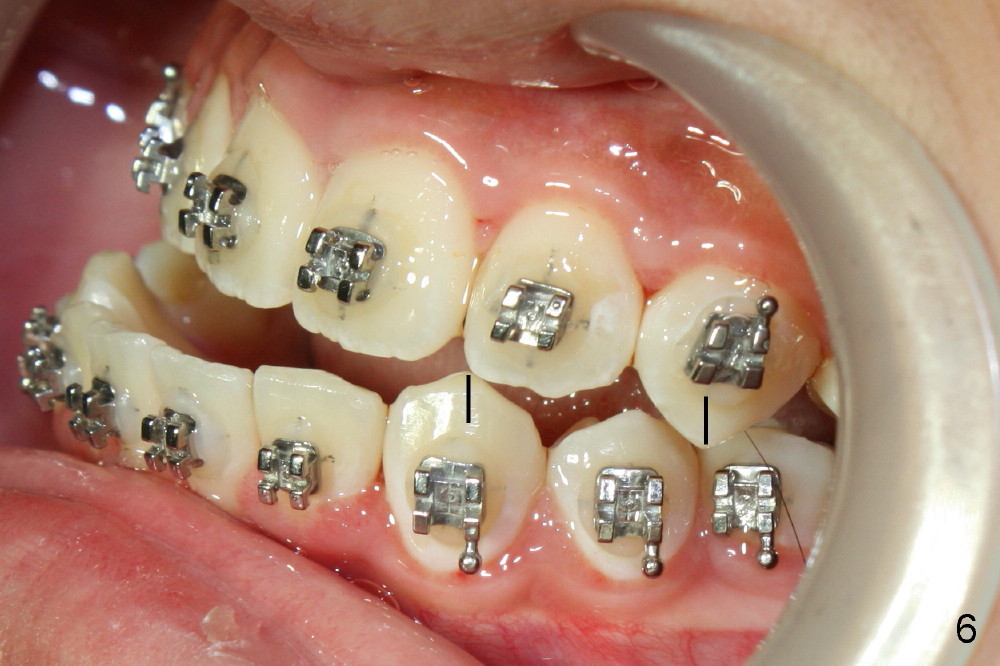

Again due to lack of close monitoring (summer vacation in China), overcorrection occurs (Fig.4-6): from Class II malocclusion to Class III (especially left side (Fig.6 black lines) with anterior open bite and midline shifting (Fig.4 white lines).